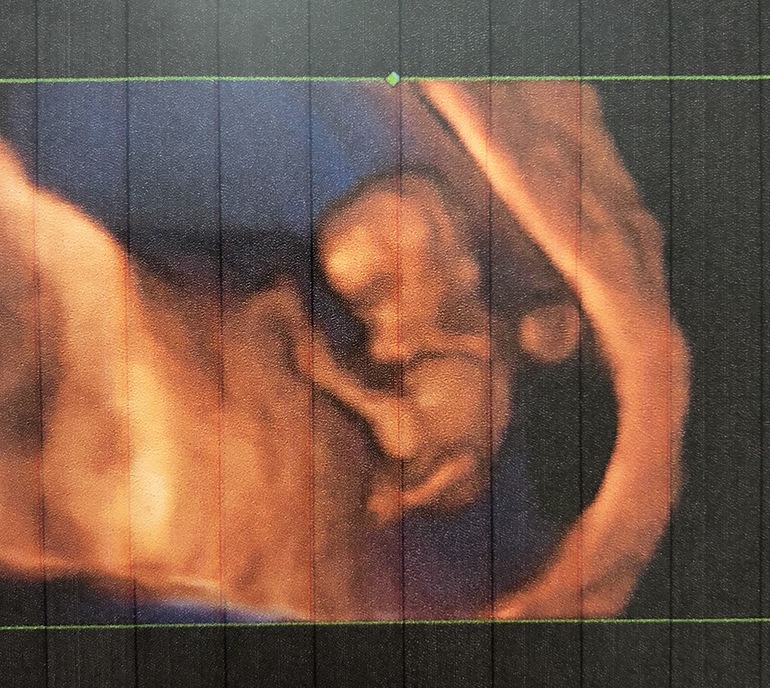

Узи 9+1

Была на узи, сегодня 9+1 акушерских недель.

Цикл 24-27 дней. Там же прослезилась. Видела своего малышастика. Моего маленького бурундучка, ручками шевелил. Опережает на неделю, по узи поставили 10+1. Ктр 32 мм, ПЯ 59 мм, сб 172 уд/мин, ЖМ 4,2 мм. Все в норме, никакой гематомы и отслойки нет, как написала другая узистка в 6+5 н.